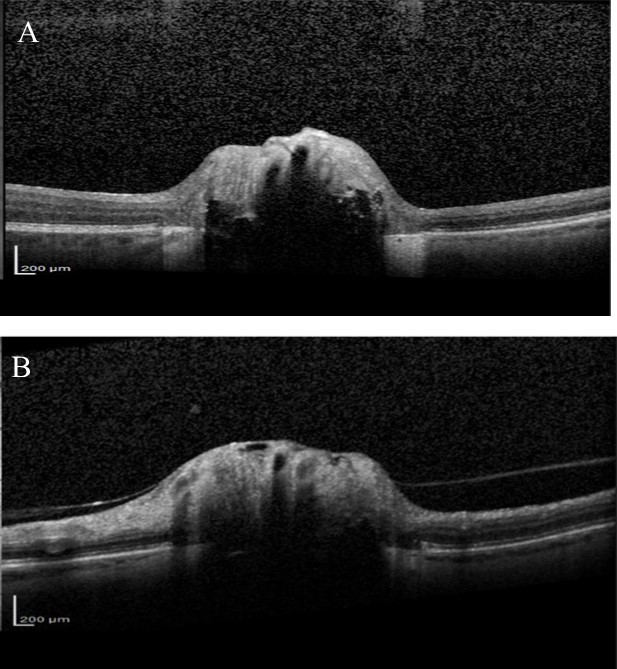

Over the next 6 months she felt the deterioration in vision in right eye had stabilised but complained that the vision in her left eye was gradually worsening. Visual acuity remained good but visual field testing confirmed a deterioration showing there had been a marked decline in the left eye visual field with MD deterioration from -9.59 to -24.01(Figure 4). Blood tests were taken for common Leber’s hereditary optic neuropathy mutations, which were negative. Vitamin B12 and folate levels were within normal range. Fundus fluorescein angiography (FFA) was also performed, looking for possible associated anterior ischaemic optic neuropathy (AION), but no evidence of late leakage was found. OCT examination of the RNFL was also performed and showed significant thinning in both eyes (Figure 5). Average RNFL thickness was only 57 um in the right eye but measured 87 um in the left, although the inferotemporal sector was outside normal limits in the left eye. Enhanced depth imaging (EDI) OCT was also performed to better ascertain the location and extent of the ONHD (Figure 6). Electro-diagnostic tests showed reduced amplitudes and prolonged latency on the visual evoked potential (VEP) for both eyes, with a normal electroretinogram. The reduced amplitude and prolonged latency on the VEP was suggestive of a non-demyelinating optic neuropathy.

Figure 6.EDI-OCT

EDI-OCT

Most previous cases of rapid visual loss in ONHD have been associated with an acute vascular event or choroidal neovascualarization. We performed FFA to investigate for secondary causes of visual loss and to look for disc leakage, however FFA was normal. Reduced amplitude and prolonged latency on the VEP, with a normal electroretinogram, suggested visual loss was due to an optic neuropathy. This is in agreement with previous studies, which have shown patients with ONHD to have prolonged latency on VEPs18, 19, 20, a finding consistent with a mechanical compressive mechanism of axonal damage. The prolonged latency and reduced amplitude in our patient was likely due to the marked extent of the nerve damage 21. Although our patient had marked ONHD, as evident from the EDI-OCT, B scan ultrasonography and autofluorescence, it is not possible to be certain that ONHD was the sole cause of visual deterioration. It is conceivable that she also had coexisting normal tension glaucoma, however the rapid deterioration in visual field would not be characteristic of this condition. Given the difficulty of diagnosing glaucoma in patients with ONHD, and the possible increased risk of IOP-mediated RGC injury in an already compromised eye, we opted to treat our patient with topical IOP lowering medication7,22.

Improvements in technologies such as EDI-OCT and Swept Source OCT might enable better identification of glaucomatous changes in eyes with ONHD as they allow imaging of deep ocular structures13,24,25. The ability of EDI-OCT to image structures 500-800 um deeper than conventional OCT allows the posterior limit of the drusen to be imaged13. Several studies have recently shown that using EDI-OCT or Swept Source OCT it is possible to visualise the extent of ONHD and to examine the thickness of neighbouring neural tissue13. Our patient had marked RNFL loss on SDOCT, particularly in the right eye. The RNFL thickness was outside normal limits, however, normative databases should be interpreted with caution in eyes with ONHD particularly as the risk of segmentation errors is likely to be higher due to abnormal anatomy. Although glaucomatous RNFL thinning characteristically involves the inferior-temporal and superior-temporal circumpapillary RNFL, the pattern of RNFL loss may not help differentiate whether this is related to ONHD or glaucoma as the location of RNFL defects associated with ONHD is likely to vary depending on location of the ONHD.